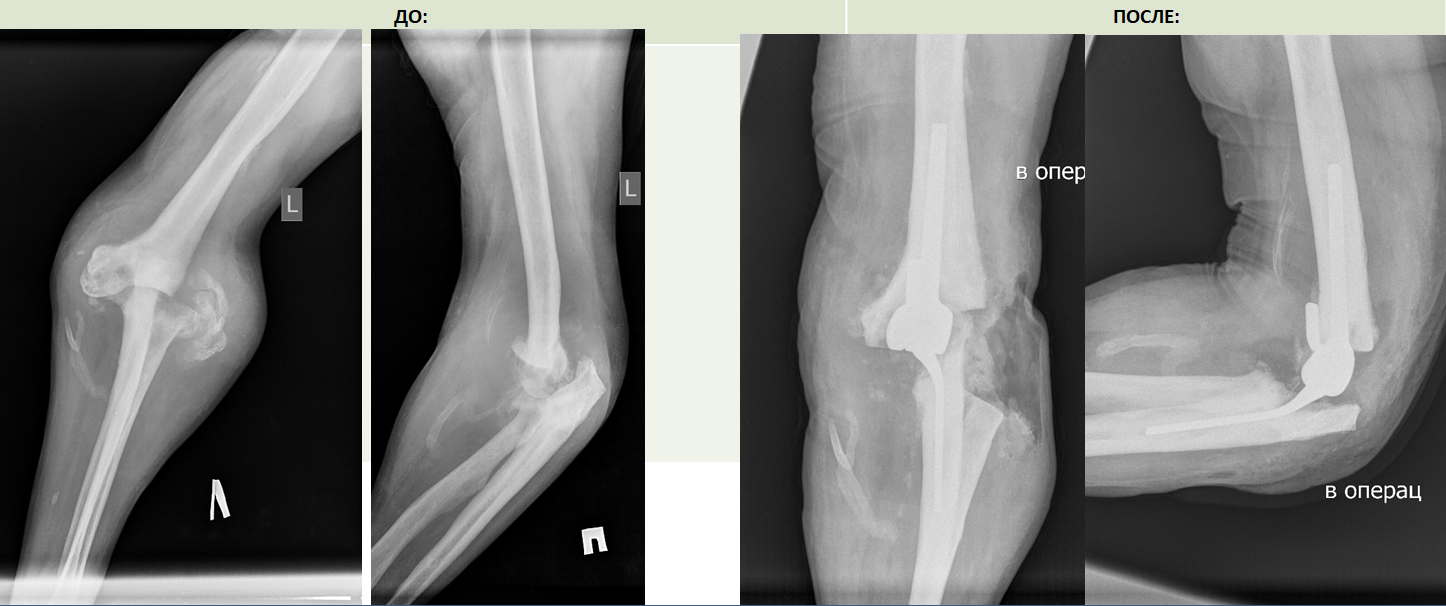

- Пациент из Томска с крайне редкой патологией сустава- артропатией Шарко, приехал в Центр Илизарова с надеждой избавиться от многолетней боли. В Клинике реконструктивно-восстановительной хирургии крупных суставов 68-летнему пациенту тщательно удалили все патологически измененные ткани и заменили пораженный локтевой сустав на эндопротез.